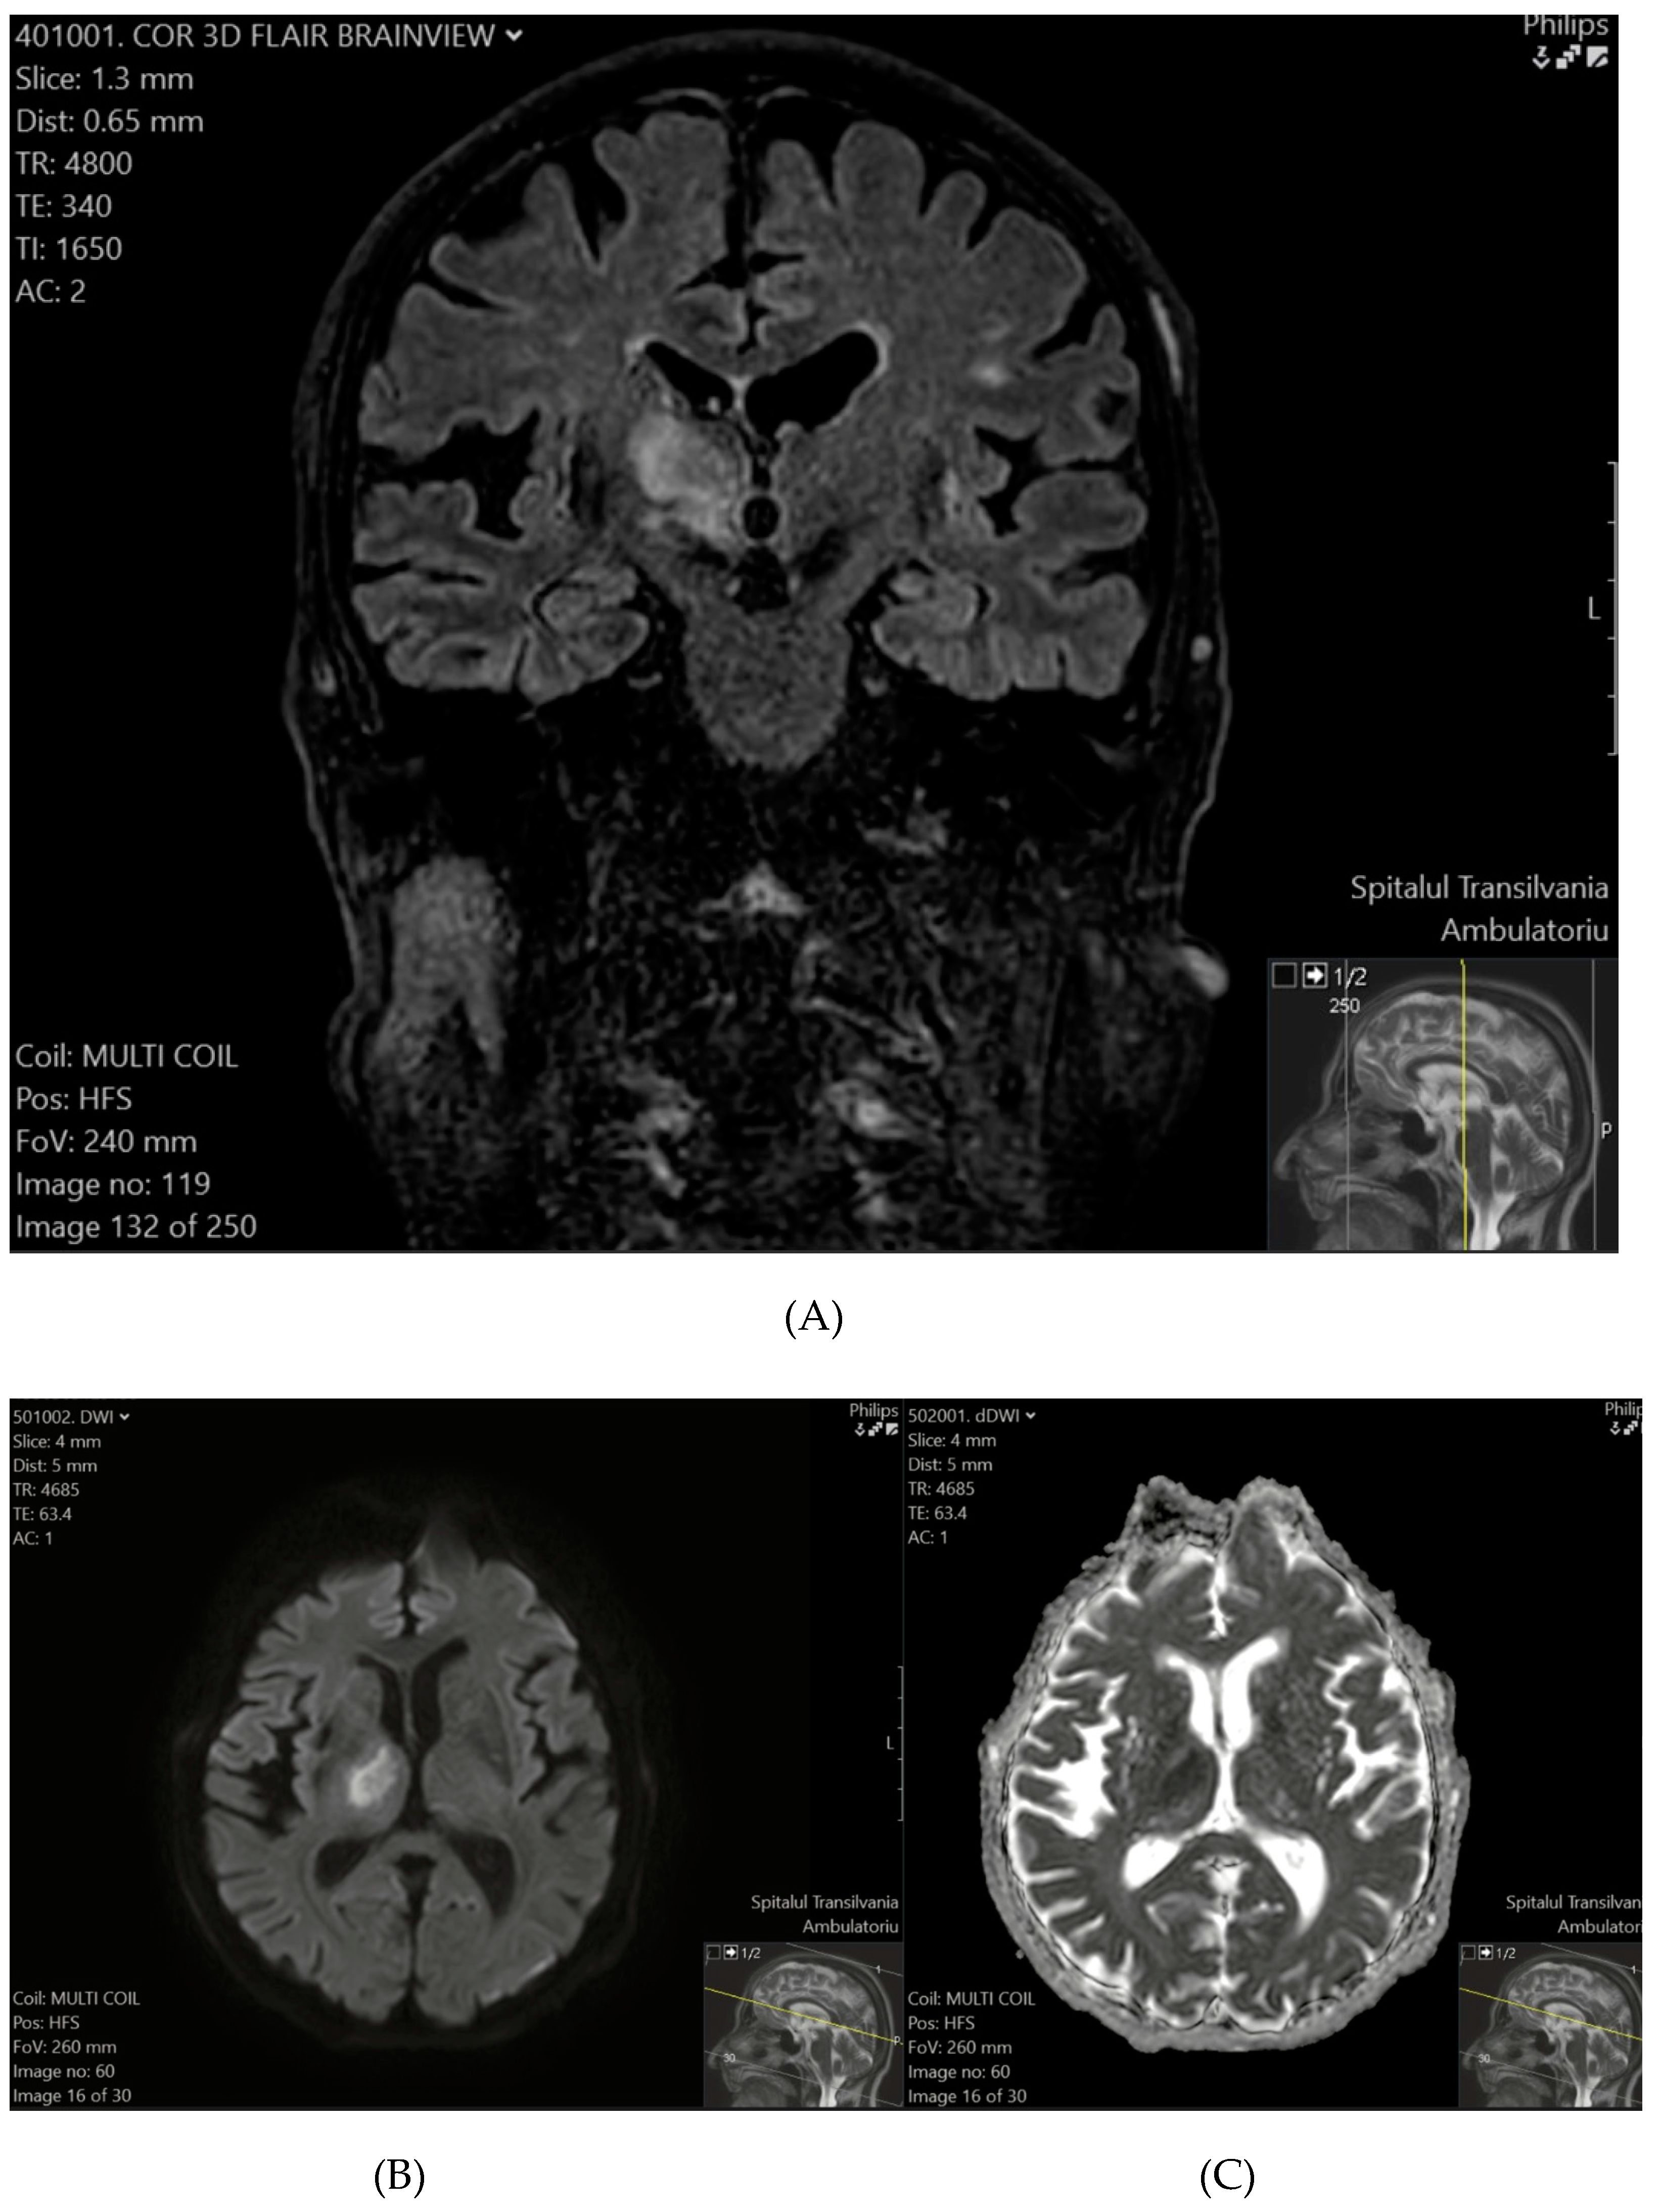

Patient 2 exhibited a hyperintense lesion in the right thalamus and the posterior limb of the internal capsule on T2-FLAIR (Figure 2A), with restricted diffusion on DWI and ADC sequences (Figure 2B,C), consistent with a recent ischemic event.

Figure 2. (A) (top) T2-FLAIR shows a hyperintense lesion in the right thalamus and the posterior limb of the internal capsule. (B) (bottom-left), (C) (bottom-right) DWI (B) and ADC (C) sequences confirm diffusion restriction, consistent with a recent ischemic event.